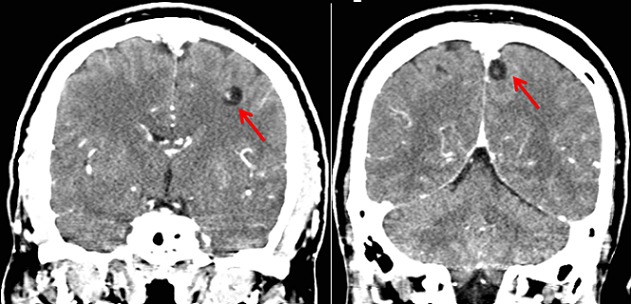

Patient K.M, âgé de 38 ans, présente des crises convulsives qui auraient débuté il y a 3 ans et s'ccompagnaient de chute, de perte de mémoire et d'oubli. Pendant environ deux ans, aucune prise en charge n′avait été instaurée mais une année avant la présente consultation, le patient fut soumis sous un traitement fait de la carbamazépine (deux fois 200 mg par jour). Cinq mois après, vu que la monothérapie ne donnait pas de résultats escomptés, une multithérapie antiépileptique (carbamazépine, phénobarbital et valproate de sodium) lui fut administrée pendant plus de sept mois mais sans succès également. Voyant que son état ne s'améliorait pas, il consulte le Centre Neuro-psychiatrique Dr Joseph-Guislain en date du 21 juin 2014. Ses antécédents ne relèvent rien de particulier et aucune crise épileptique n′a été retrouvée dans sa famille. Mais il faut signaler que dans ses habitus, il consomme régulièrement la viande de porc. Au complément d′anamnèse, nous notons que ses crises convulsives sont focales évoluant vers des crises bilatérales avec des composantes toniques et cloniques. Pendant les crises, il y a une émission d′écume et une perte d'urine. Elles durent environ 5 minutes et ont une fréquence de 2 à 4 par mois. L′examen neurologique était normal. L’électroencéphalogramme montre un tracé perturbé par sa lenteur et par l′abondance en éléments lents à prédominance droite. Le scanner cérébral met en évidence au niveau du parenchyme des multiples lésions kystiques arrondies avec un point hyperdense excentrique représentant le scolex (Figure 1,Figure 2 et Figure 3). Nous avons conclus à une NCC révélée par une épilepsie réfractaire. Après un examen normal du fond d’æil, nous avons instauré un traitement par voie orale fait d'Albendazole (15 mg/kg/jour en 2 prises) et de Prednisolone (1 mg/kg/j) pendant une durée d'une semaine. Un suivi médical pendant une durée de six mois a été fait et aucune crise épileptique n'a été notée jusqu’à ce jour.

Figure 2.

Scanner cérébral montrant multiples cysticerques viables et sans œdème (coupe coronale)

Il est difficile de déterminer la prévalence et l'incidence de la NCC en raison de la non-spécificité de sa manifestation clinique et l'absence de tests de laboratoire qui peuvent être utilisés pour confirmer le diagnostic à grande échelle. La majorité des personnes ayant la NCC sont asymptomatiques [6]. Dans une étude menée à Kinshasa (RDCongo), le diagnostic de NCC avait été retenu chez 11 patients sur un total de 4233 scanners cérébraux réalisés en 15 ans soit une fréquence de 0,26% [7]. Malgré que la RDCongo fait partie des pays à haute prévalence de NCC [8], cette pathologie est de diagnostic plutôt rare en milieu urbain. Le diagnostic précis de la NCC repose sur l′évaluation de données objectives de la clinique, de l'imagerie, de l'immunologie et de l’épidémiologie. Ces données ont été regroupées en quatre catégories de critères: absolus, majeurs, mineurs et épidémiologiques [9]. S'agissant de notre cas, le diagnostic de NCC était basé sur la présence de lésions kystiques montrant le scolex sur les images du scanner cérébrale, la présence de signes cliniques évocateurs de NCC (épilepsie faite des crises convulsives focales évoluant vers des crises bilatérales), la réponse clinique au traitement à l'albendazole et le fait que notre patient vit dans une zone reconnue endémique à la cysticercose. Sur le plan histo-pathologique, il y a quatre stades évolutifs de la NCC: vésiculaire, colloïdale, granuleuse (ou nodulaire) et calcifiée [9]. Dans notre cas, l'imagerie est suggestive de l′étape vésiculaire qui apparait comme des petites kystes arrondies qui sont bien délimitées du parenchyme cérébral qui ont dans leur intérieur un nodule hyperdense excentrique représentant le scolex donnant l'aspect d'un “trou-avec-point” (hole-with-dot) tel que le décrit les anglophones, qui est pathognomonique de la NCC [10]. Ce stade vésiculaire est observé lorsque les cysticerques atteignent le système nerveux central et peuvent rester à ce stade pendant plusieurs années [9].